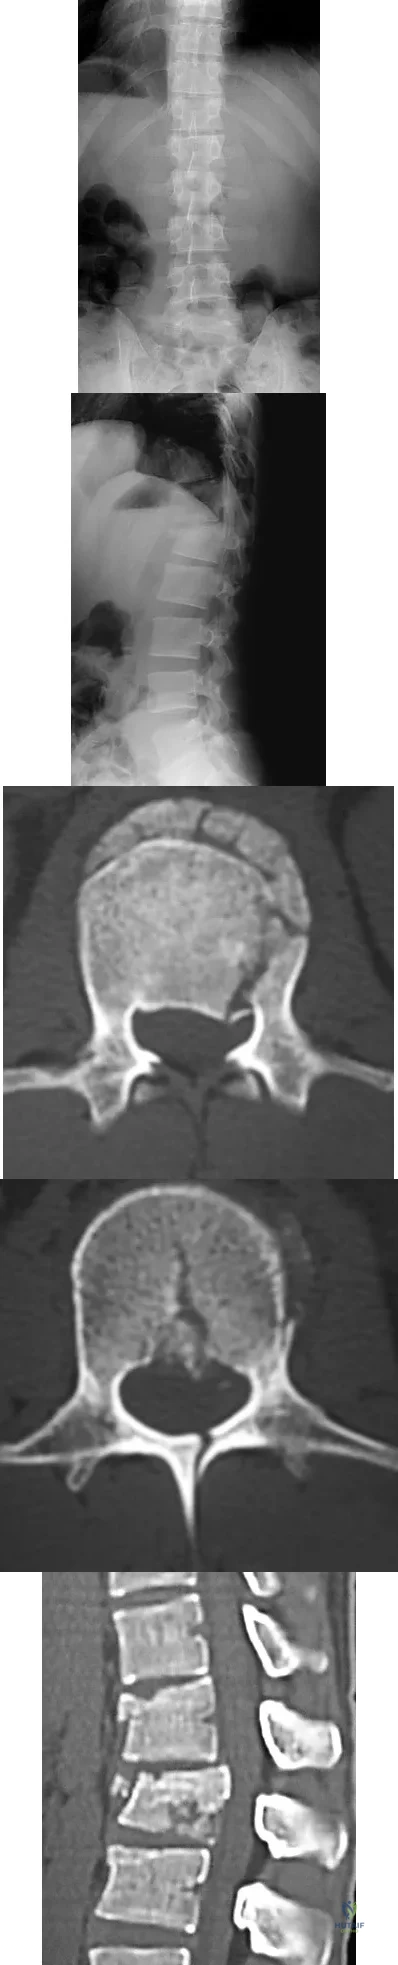

Question 66

Figure 12 shows the lumbar CT scan of a 24-year-old man who was injured in a snowmobile accident. What is the mechanism of injury?

Explanation